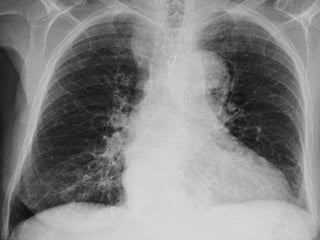

TELERADIOGRAFIA DE TX.

MARCADOR

CRITERIOS DE EVALUACION RX.

TX.

 Pulmones desde ápex

hasta senos costo

diafragmáticos

   Pulmones y corazón sin

rotación.

   10 pares de costillas.

   Sombra área de la

tráquea centrada sobre

la columna.

   Balance en los

contrastes de la imagen

(exposición adecuada).

INTERPRETACION

 Revisar estructuras

óseas.

   Partes blandas.

   Espacios intercostales.

   Parénquima pulmonar

   Nivel de los senos

costodiafragmaticos.

   Neumatización.

   Trama alveolo-pulmonar

   Silueta cardiaca

   Cayado aórtico.

CRITERIOS DE EVALUACIONRX. TX.  Pulmones desde ápex hasta senos costo diafragmáticos  Pulmones y corazón sin rotación.  10 pares de costillas.  Sombra área de la tráquea centrada sobre la columna.  Balance en los contrastes de la imagen (exposición adecuada).

INTERPRETACION  Revisar estructuras óseas.  Partes blandas.  Espacios intercostales.  Parénquima pulmonar  Nivel de los senos costodiafragmaticos.  Neumatización.  Trama alveolo-pulmonar  Silueta cardiaca  Cayado aórtico.